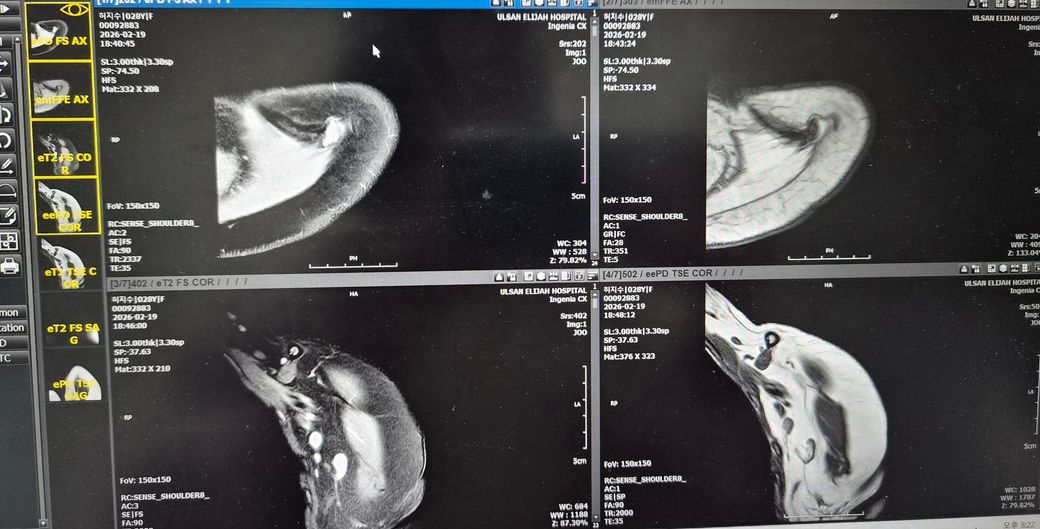

어께MRI판독좀 해주세요!어떤가요?

뺄수밖에 없었어요.누워서 안정취하다가 수납하고갔어요.그다음날 종합병원정형외과가서 접수하고 기다렸어요. 들어갔더니 의사가 힘줄에는 다 이상이 없데요.뼈가 (견봉쪽?)골절되면서 붙으면서 뼈가 위로조금 오른쪽이랑 다르게 올라갔데요 그래서 아프면 주사맞자고해서 주사대기중이였어요.옷갈아입고 기다렸어요.

랫풀다운 몇번하니깐 어께가 찌릿하고 아픈데 힘줄이 부분파열로 진행이 된걸까요? 조금찢어진건가요?

아님 뼈가 힘줄에 닿여서 마찰이 자꾸

생겨서 아픈걸까요?

올려주신 MRI사진은 화면 촬영본이라 정확한 판돈까지는 어렵지만, 담당 의사가 말씀하신 것처럼 회전근개 힘줄 자체의 명확한 완전파열 소견은 없어 보이는 경우로 이해됩니다. 설명해주신 내용상 어깨 위쪽 뼈 쪽 골절이 치유되는 과정에서 약간 위로 붙어 형태가 변형되었고, 그로인해 어깨를 들때 힘줄과 뼈 사이 공간이 좁아져 마찰이 생기는 충돌 증후군 형태일 가능성이 높아 보입니다. 주사 치료는 보통 염증을 줄이기 위한 스테로이드+국소 마취제 주사이며, 약물이 하얗고 양이 많으며 들어갈때 아픈것은 비교적 흔합니다. 주사 맞은 당일저녁에 헬스장에서 찌릿한 통증이 생긴것은 힘줄이 새로 찢어졌다기보다는 주사 후 자극+기존 충돌부위 자극 때문일 가능성이 훨씬 큽니다. 현재로서는 최소 1주일 정도는 상체웨이트 운동을 쉬고, 얼음찜질과 가벼운 가동범위 운동만 하는것이 좋습니다. 이후 통증이 줄어들면 가벼운 밴드 운동부터 재개하는 것이 안전합니다. 빠른쾌유를 빕니다!

• "주사 직후 헬스(랫풀다운)"로 찌릿한 통증이 생긴 건 "힘줄 부분파열 가능성은 낮고" 주사 자극 + 염증 부위 과부하로 보는 게 더 타당합니다.

• 의사 말대로 "견봉 쪽 골절 후 변형된 뼈가 힘줄과 마찰"하면서 통증이 재현됐을 가능성이 큽니다.